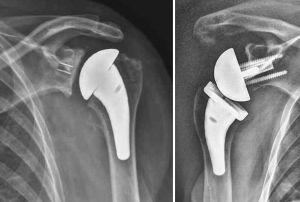

Lorsque l’arthrose de l’épaule, ou omarthrose, atteint un stade avancé où le traitement médical ne parvient plus à soulager la douleur et la perte de